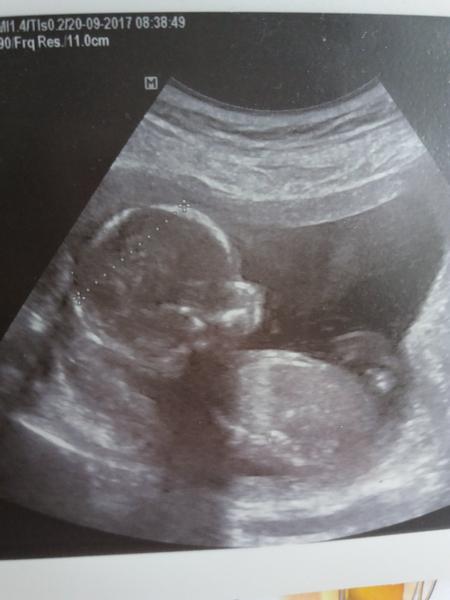

Ahoj maminky a budoucí maminky 😉 Prosím, poradila byste mi některá, co vidíte na fotce z ultrazvuku ve 20. týdnu za pohlaví? Určitě jste foteček viděly už mraky, proto vás žádám o radu...Nechci nikoho ovlivnit, proto svůj tip řeknu později 🙂 Děkuju moc!!!

ja bych podle hlavičky rekla, že to bude holcicka, ale dulezity je videt dolu 🙂

Pan doktor právě taky tipoval holčičku. Uvidíme na velkém utz ve 20.týdnu, zda se potvrdí 🙂 Děkuji za odpověď.

Nene holky,je to jasný chlapeček 😂 Na tý první fotce je vidět i pindík,který je jakoby u spodního stehýnka (nahoru teda vede pupečník)